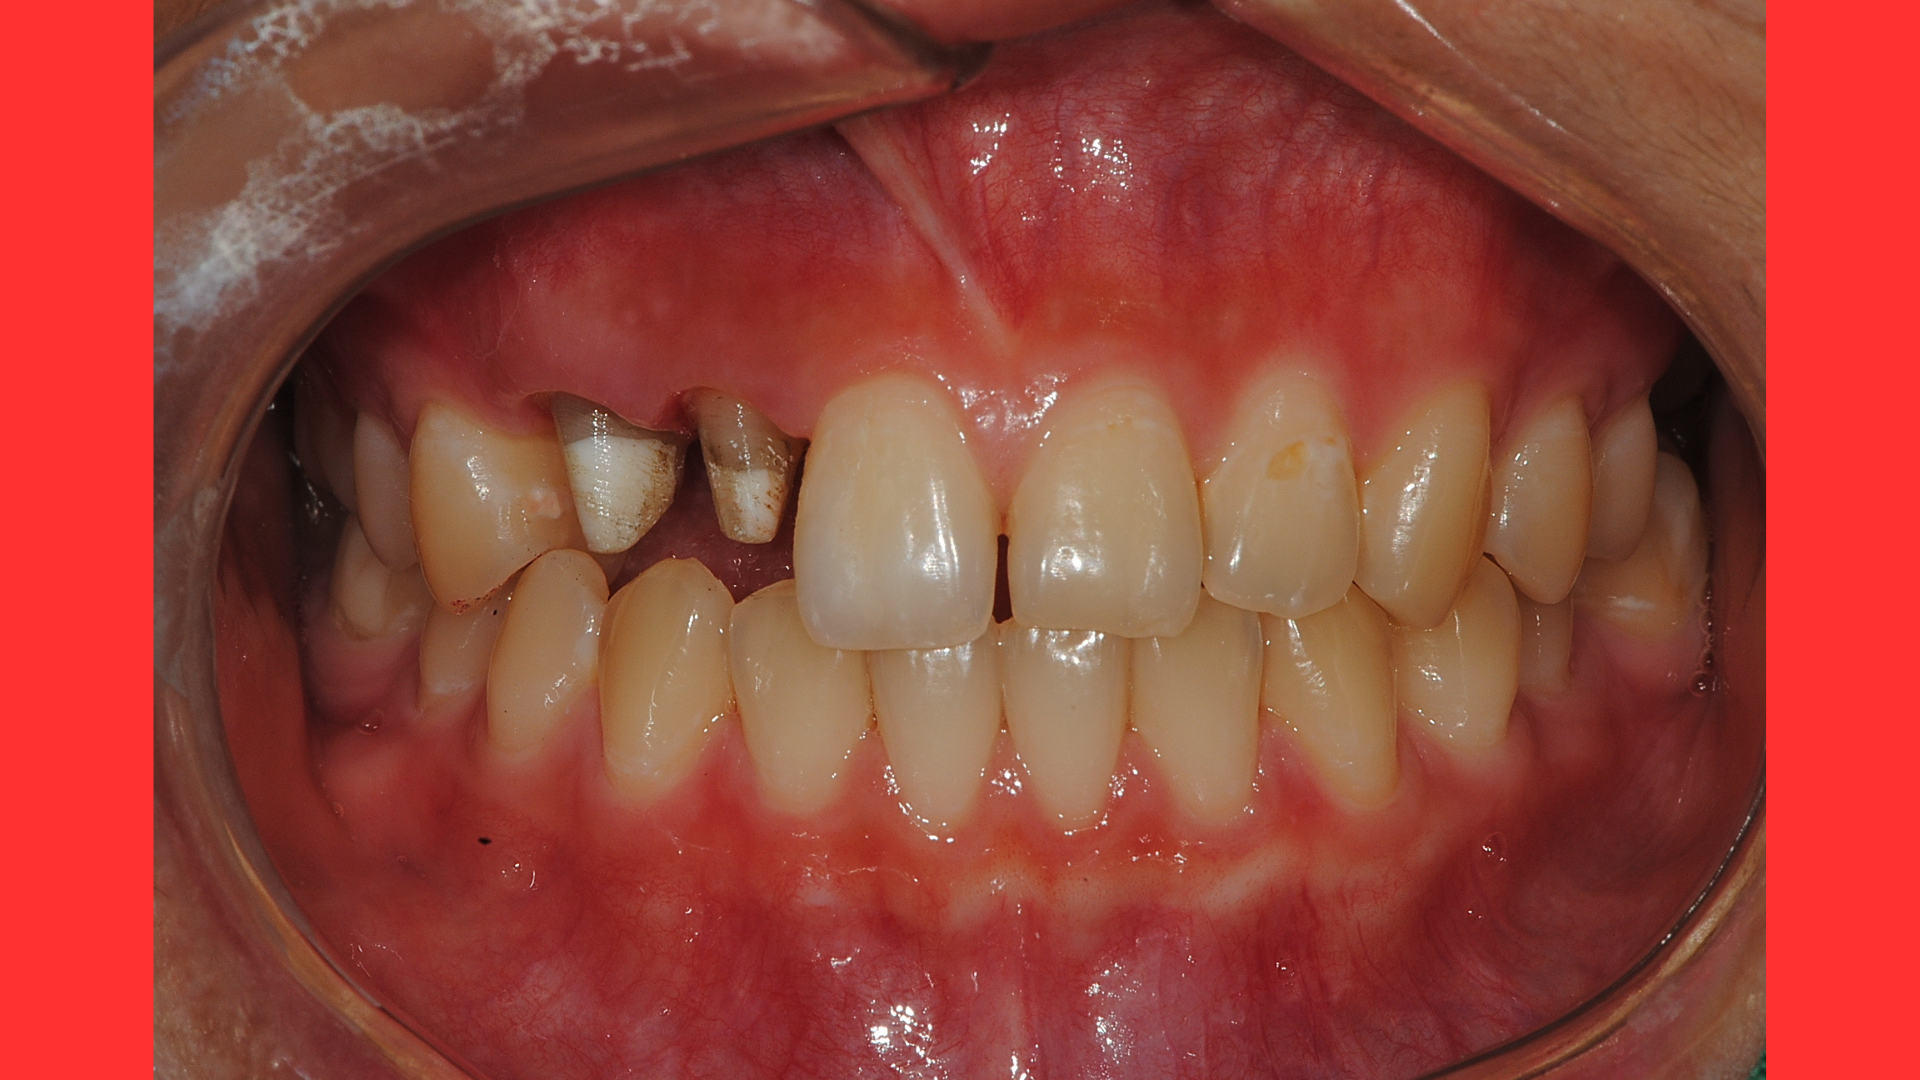

두번째 보이는 부분을 보시면 우리가 볼때 왼쪽과 오른쪽의 충치가 있는 치아의 잇몸높이가 다릅니다.

충치가 깊지만 생물학적 폭경을 확보하면서도 잇몸선을 맞출 수 있는 동시에 할수 있는 수술이 결국은 골삭제를 동반한 치관확장술이 되는 것입니다.

다음 사진은 치관확장술을 진행후 1달뒤의 사진입니다.